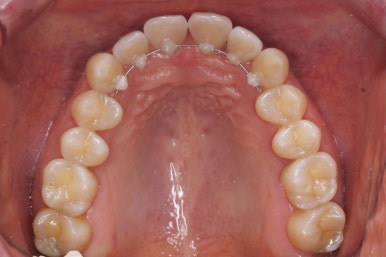

마찬가지로 부산설측교정 키다리아저씨치과에서 처음 내원하셨을 당시의 입안 모습입니다.

어금니쪽은 특별히 이상이 없었고, 위아래 앞니만 삐뚤한 상태였습니다.